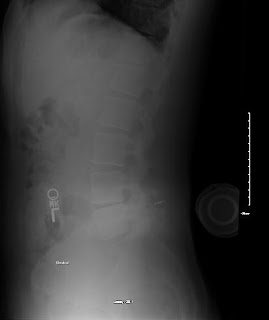

Had my 2 year follow up with MRI and X-ray's last week and I have posted the images below. The surgeon (Dr V) was surprised that the L4 and L5 bones showed signs of improved health ( 2 years ago they both took a beating from the wear and tear on them). The disc is still degenerating but it's seems to have slowed somewhat.

Below are the MRI and X-Ray images:

(X-Ray courtesy of BCH)